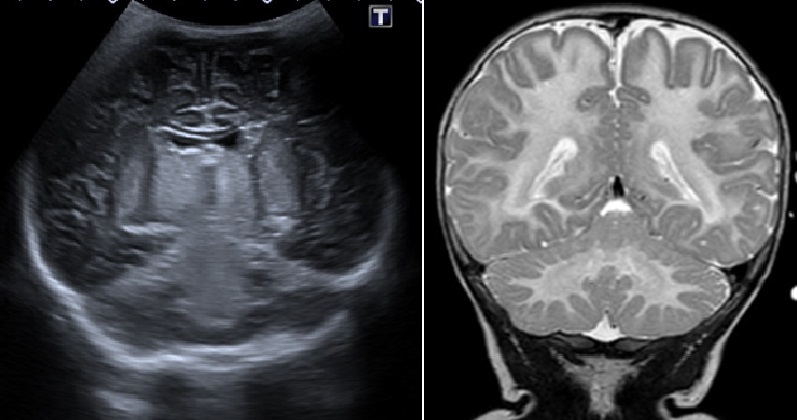

Canavan gaixotasuna haurtzaroko eritasun neurodegeneratibo genetiko eta metaboliko arraroa da eta ikusmen-nahasmenduak, akats neurologikoak eta ondorio larriak eragin ditzake. Ez dago tratamendu sendagarririk, baina litio zitratoa ikertzen ari dira. Euskal Herrian diagnostikatu den Canavan gaixotasunaren lehen kasuaren eta Europan lehenbizikoz aurkitutako mutazio berri baten aurkezpena egin dugu.